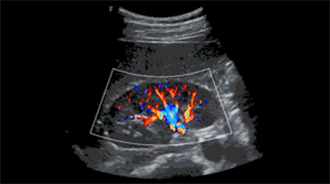

微血流成像

传统

并行16波束